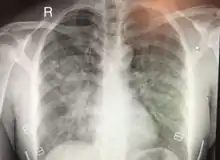

| Chest x-ray of HAPE showing characteristic patchy alveolar infiltrates with right middle lobe predominance. | |

Hypoxic pulmonary vasoconstriction (HPV) occurs diffusely, leading to arterial vasoconstriction in all areas of the lung. This is evidenced by the appearance of "diffuse," "fluffy," and "patchy" infiltrates described on imaging studies of climbers with known HAPE.[9]

On physical exam, increased breathing rates, increased heart rates, and a low-grade fever 38.5o C (101.3o F) are common.[9][3] Listening to the lungs may reveal crackles in one or both lungs, often starting in the right middle lobe.[9][3] Imaging studies such as X-ray and CT imaging of the chest may reveal thoracic infiltrates that can be seen as opaque patches.[14][9][3] One distinct feature of HAPE is that pulse oximetry saturation levels (SpO2) are often decreased from what would be expected for the altitude. People typically do not appear as ill as SpO2 and chest X-ray films would suggest.[9][3] Giving extra oxygen rapidly improves symptoms and SpO2 values; in the setting of infiltrative changes on chest X-ray, this is nearly pathognomonic for HAPE.[3]